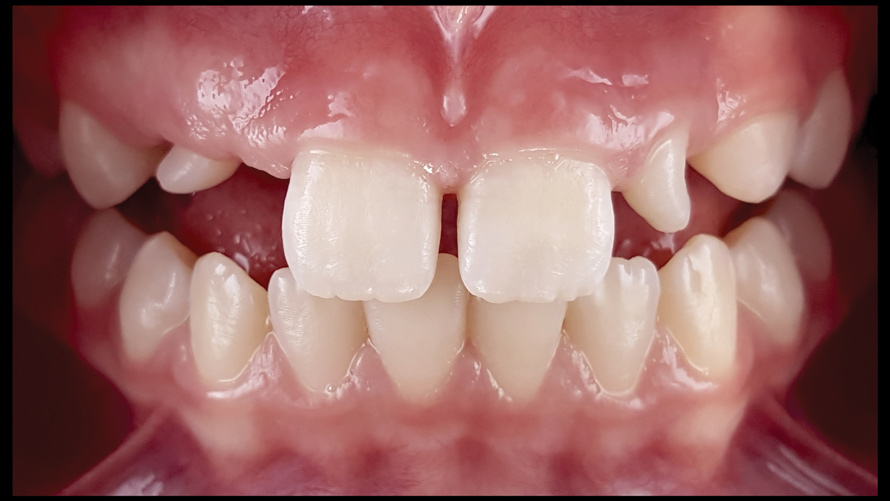

(9.) Preoperative esthetic case documentation using a smartphone and an EALS device.

Figure 9

(10.) Preoperative esthetic case documentation using a smartphone and an EALS device.

Figure 10

(11.) Preoperative esthetic case documentation using a smartphone and an EALS device.

Figure 11

One of the main advantages that smartphone cameras have over DSLR cameras is that nearly everyone is already very familiar with the technology; therefore, the incorporation of these devices into everyday practice does not require learning a new and unfamiliar skill set. The task of producing a series of high-quality clinical photographs for routine examinations (Figure 8), esthetic treatment planning (Figure 9 through Figure 11), or specialty care (Figure 12 and Figure 13) can be delegated with confidence to any staff member during the patient's initial office visit and will generally require less than 5 minutes of time to complete. When a DSLR camera is used, evaluation of the intraoral images either takes place on the small viewfinder built into the camera or necessitates the physical removal of the memory card from the camera to downloaded the images onto a computer for review. An added bonus of smartphone dental photography is that the phone's screen now replaces the much smaller viewfinder of a DSLR camera and provides the clinician with the ability to view and zoom into the patient images on a 5- to 6-inch, high-definition display.